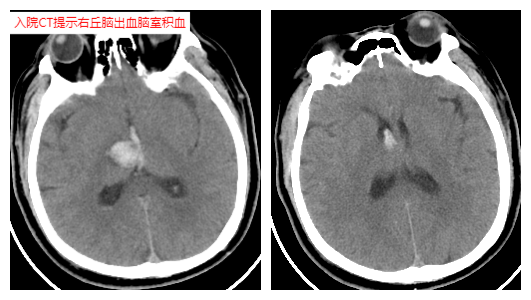

該患者最初因腦出血入住本地其他醫(yī)院,次日清晨突發(fā)心跳停止,經(jīng)心肺復(fù)蘇后緊急轉(zhuǎn)入隨州市中心醫(yī)院ICU。當(dāng)時患者瞳孔散大、呼吸衰竭、血壓極低,必須依靠大量藥物維持,CT顯示腦部出血加重,生命岌岌可危。